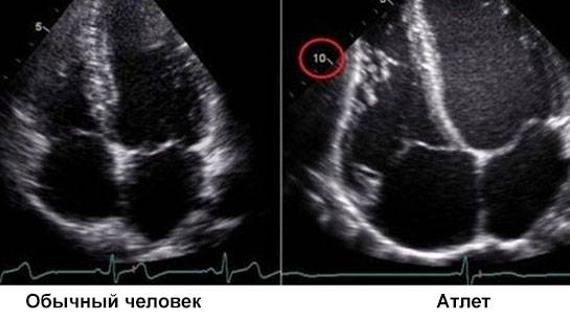

Почему бывает увеличенное сердце? Как на это влияет образ жизни и физическая активность? Какими симптомами проявляется патология и какие современные методы...

Из этой статьи вы узнаете: почему может увеличиваться сердце, всегда ли большое сердце – это признак болезни. Какие симптомы появляются, если сердце увеличено...